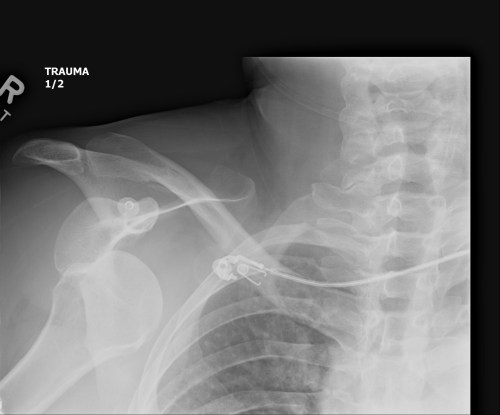

CT scan axial slice showing my neck (on left), then scapula with fractured coracoid process ("bad") and displaced, fractured greater tubercle of humerus on right side.

CT scan axial slice showing my spine (on left), then scapula with fractured coracoid process (“Bad”) and displaced, fractured greater tubercle of humerus on right side (“V bad”).